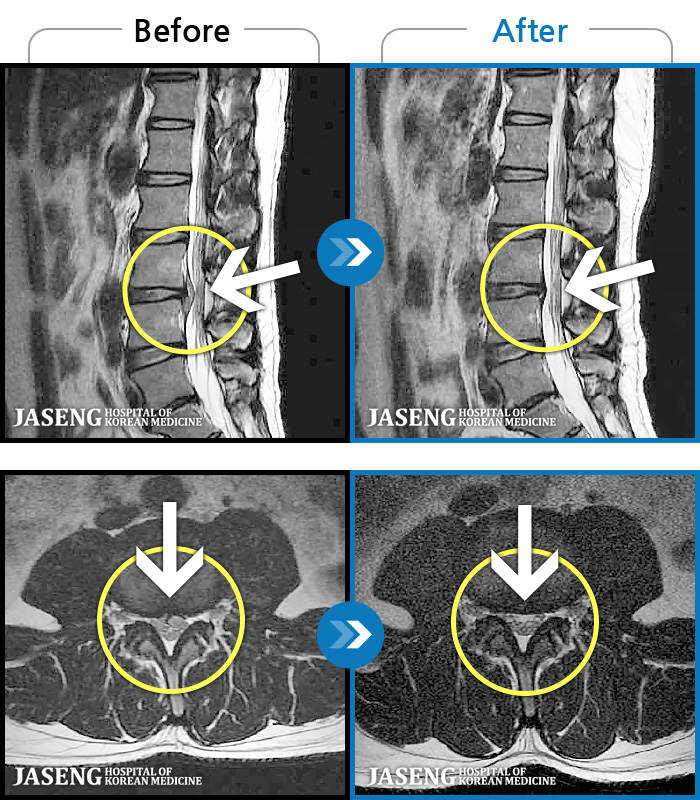

MRI ġ

1,237 MRI ũ ʸ Ȯϼ.